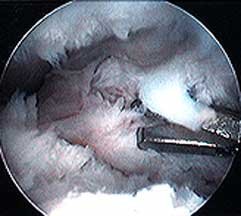

On the left - a view down the arthroscope of a normal knee, showing the rounded end of the femur (condyle), the flattened top of the tibia, and the meniscus wedged between them.

On the right - a similar view in a knee with advanced arthrofibrosis - shows a dense growth of fibrous scar tissue and overgrown synovium obscuring the normal anatomy.